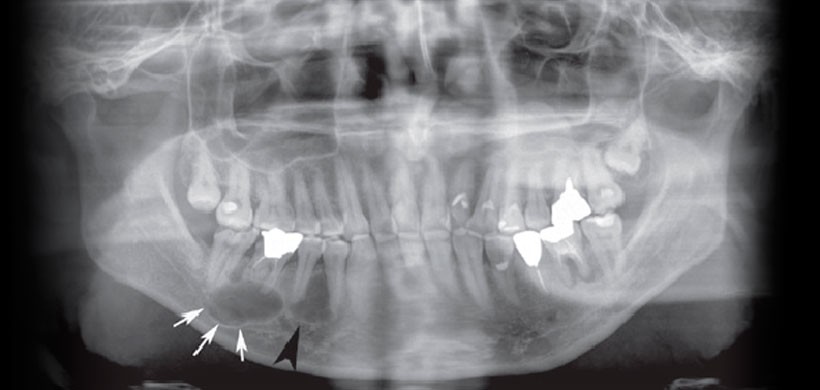

Fig 2. Imágenes de tomografía computarizada de la mandíbula del paciente. (A) Una vista axial que muestra la sección transversal de la mandíbula desde el lado derecho del paciente. Se detectó una lesión quística de 15 mm de tamaño redondo y bien definida en el ápice de la raíz del primer molar inferior derecho (flecha); Además, se identificó una lesión radiolúcida de 12 mm de tamaño en el tabique interalveolar de los premolares inferiores (punta de flecha). (B) Una vista axial demostró la divergencia radicular de los premolares inferior derecho (punta de flecha). (C) Una vista para-sagital reveló el septo dentro del ameloblastoma, así como la divergencia de los premolares inferior derecho.